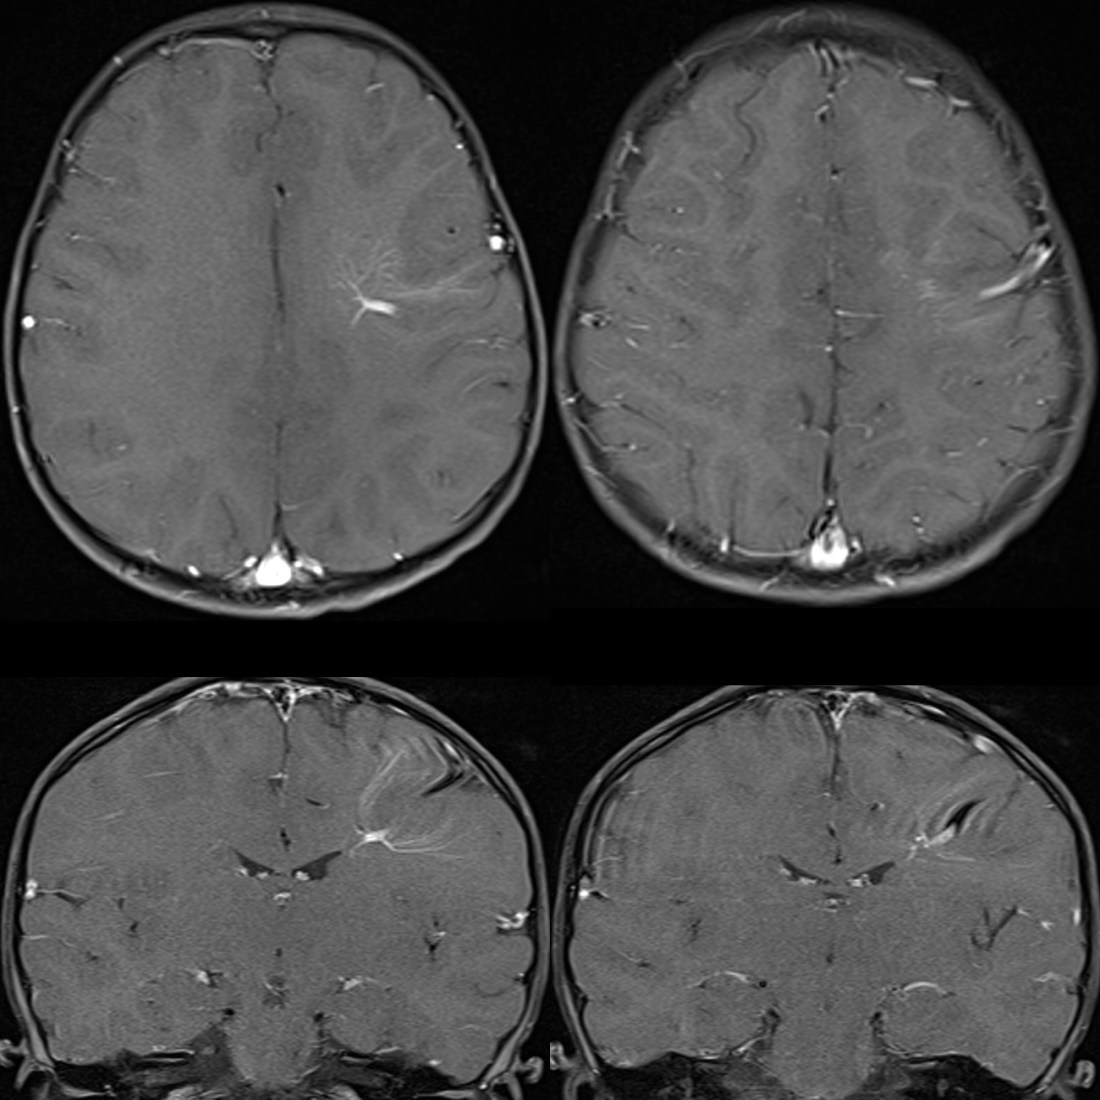

Learn about a Developmental Venous Anomaly (DVA), a common congenital brain vascular malformation. Discover why these benign venous variations are typically asymptomatic, how they appear on MRI or CT scans, and when neurosurgeons consider them clinically significant. Understand the risks and characteristics of this incidental vascular finding to better navigate your neurological health and diagnostic imaging results.

TitleClinical significance of intracranial developmental venous anomalies | Journal of Neurology ...